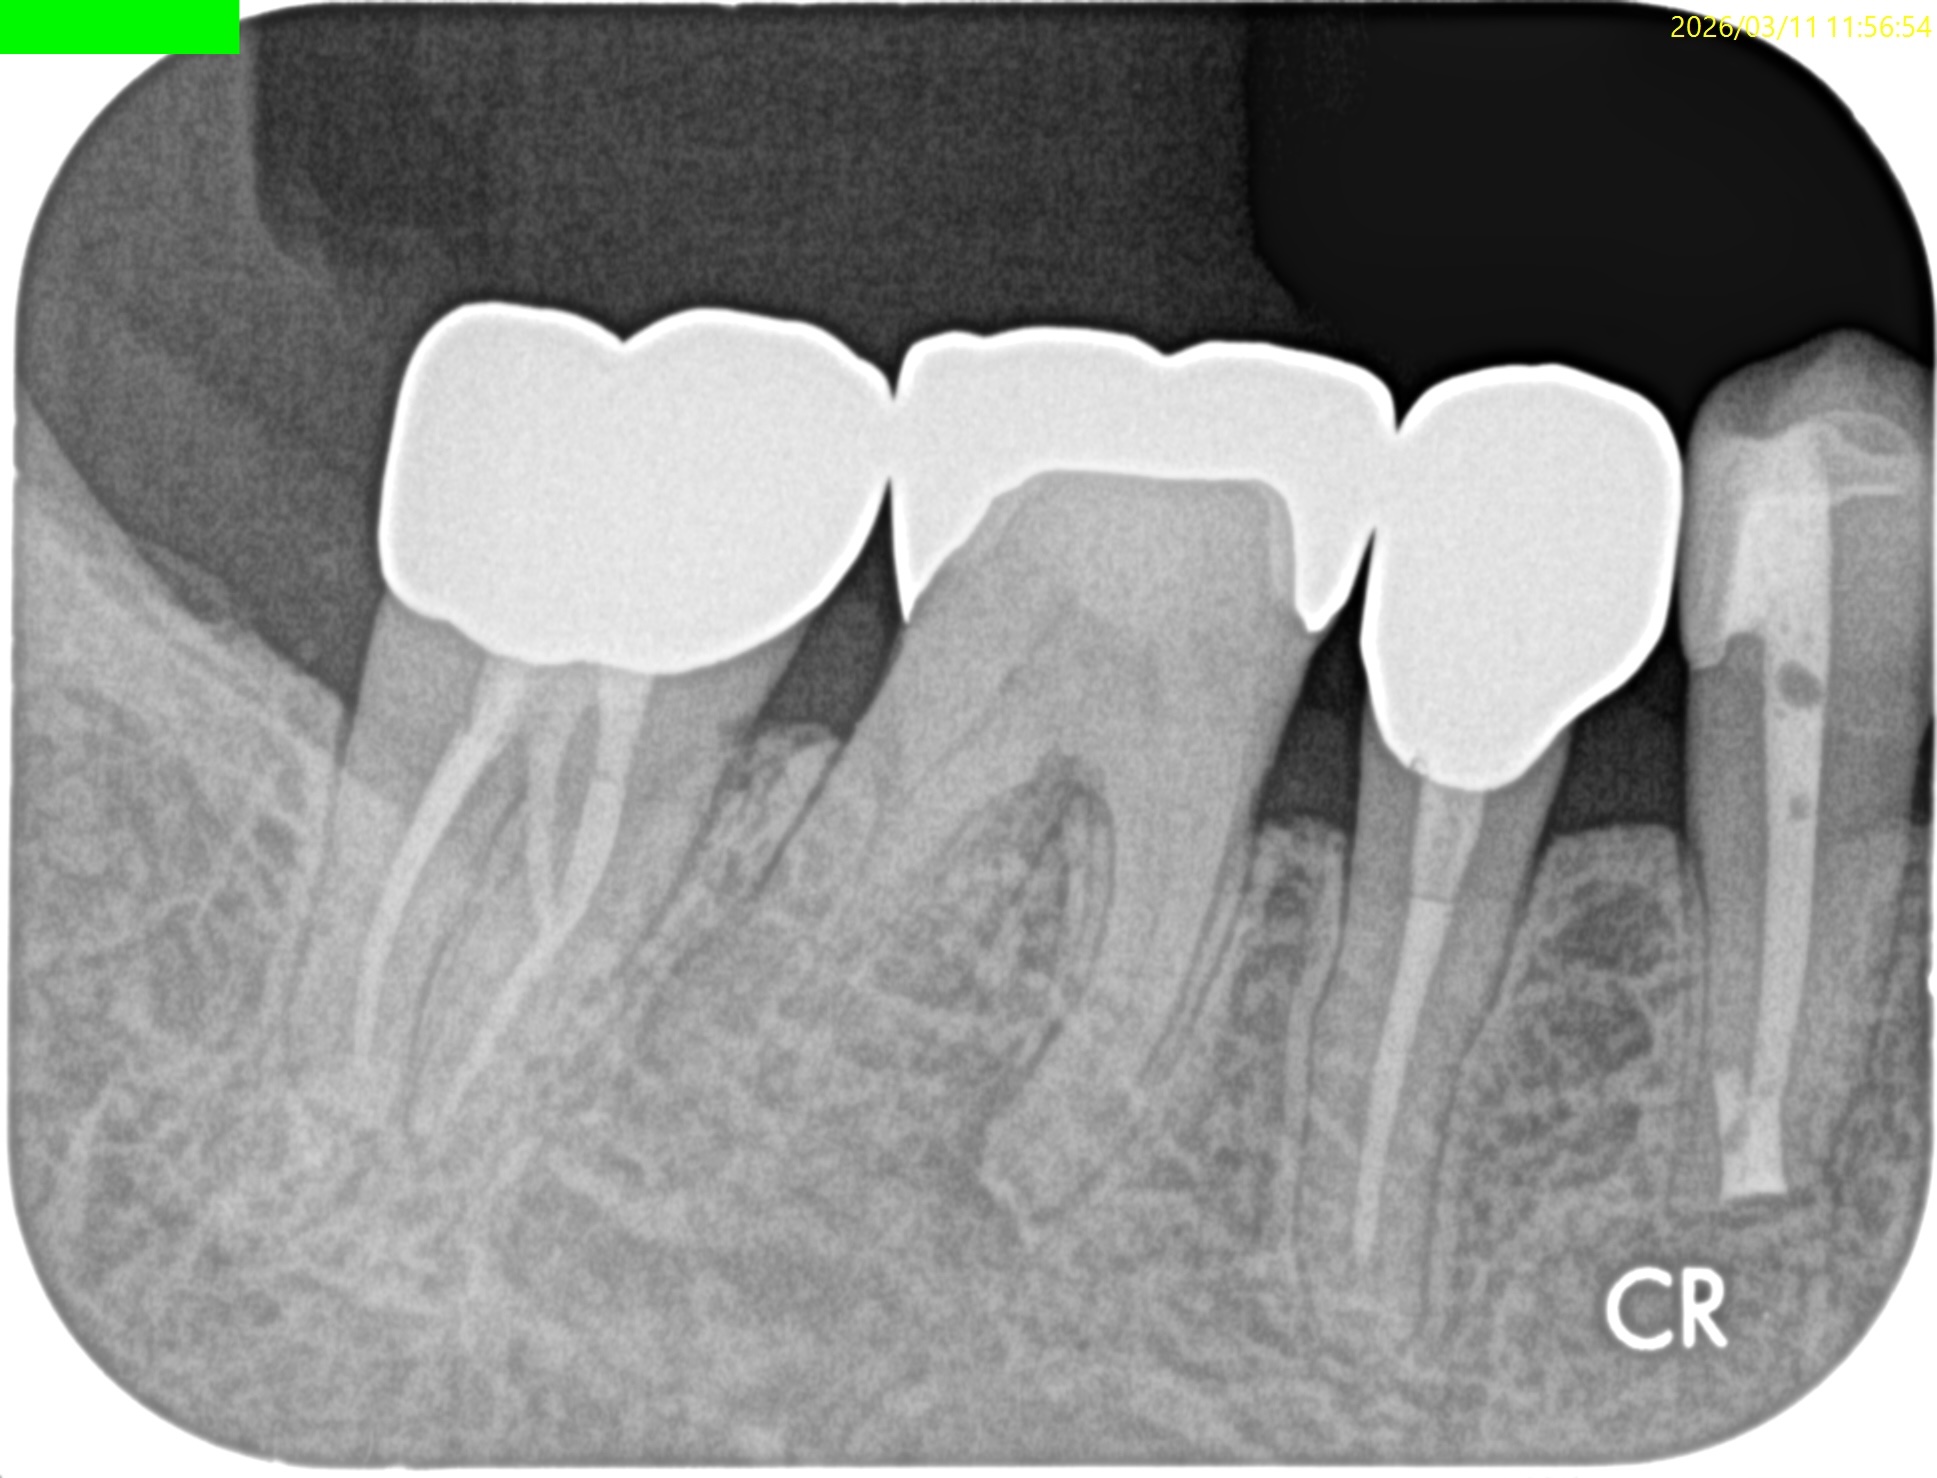

Pre-op Endo test(2026.3.11)

MB

ML

D

Radix

Gold Inlayの封鎖性を持ってしても歯髄の生活性を担保することはできなかったようだ。

ということでRadix以外の根管全てに根尖病変があり、穿通がマストだ。

が、歯髄に近い修復で石灰化が進んでいる。

SXを入れる前に短針でスカウティングが必要だろう。

またRadixも湾曲が強い。

ここも形成で工夫が必要だ。

Pulp Dx: Pulp Necrosis

Periapical Dx: Symptomatic apical periodontitis

Recommended Tx: RCT